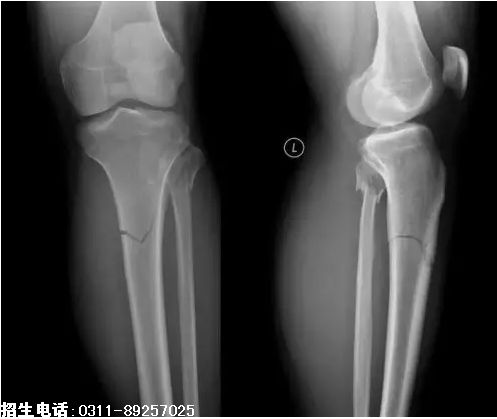

10、题干:男,56岁。左小腿外伤20分钟。结合X线片,此诊断为

A、左股骨骨折

B、左胫、腓骨双骨折

C、左腓骨骨折

D、左胫骨骨折

E、左尺、桡骨双骨折

答案:B

解析:该患者左小腿外伤,由图片可见胫腓骨透亮的骨折线,可判断该患者为胫、腓骨双骨折。(B对)